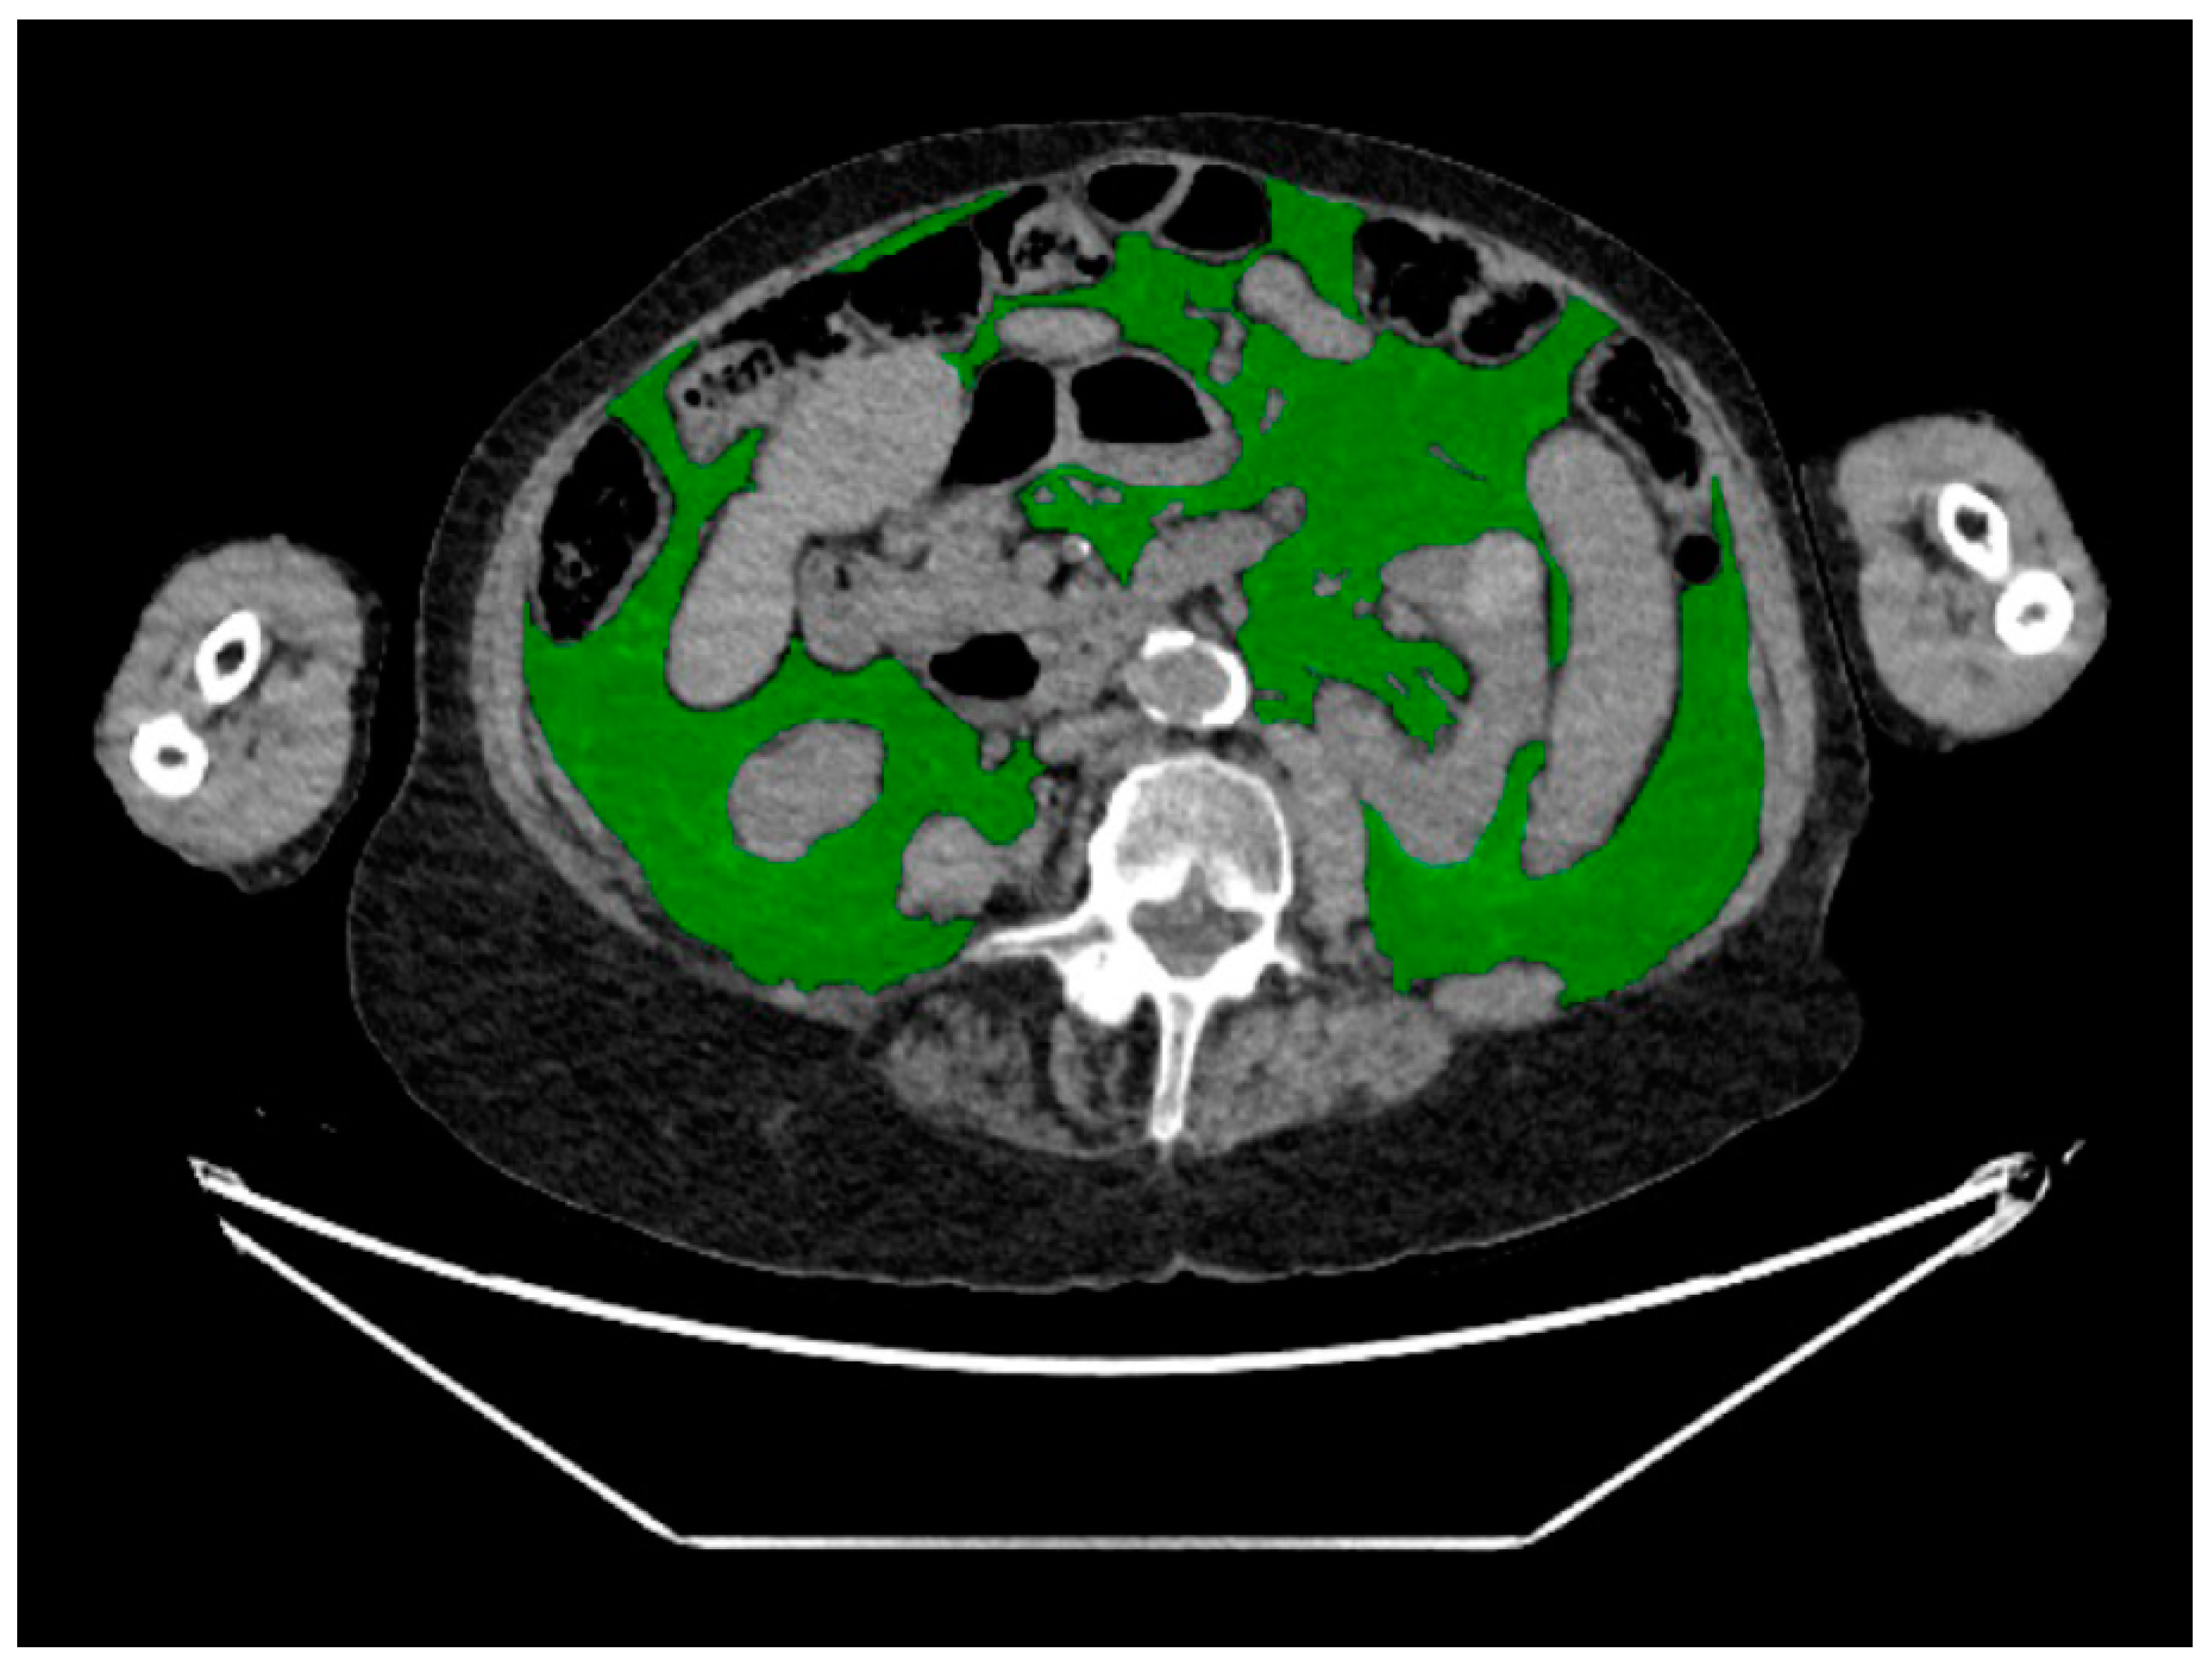

2.3. CT Body Composition Assessment

| Body composition measures a | Median (IQR) or % (n) |

| Visceral adipose tissue | |

| Area (cm2) | 124 (75–211) |